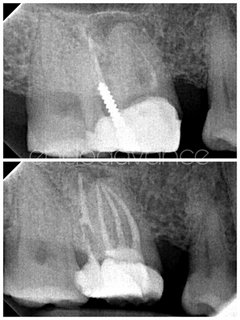

Ένδοδοντική θεραπεία σε κάτω προγόμφιο με αφαίρεση σπασμένου μικροεργαλείου